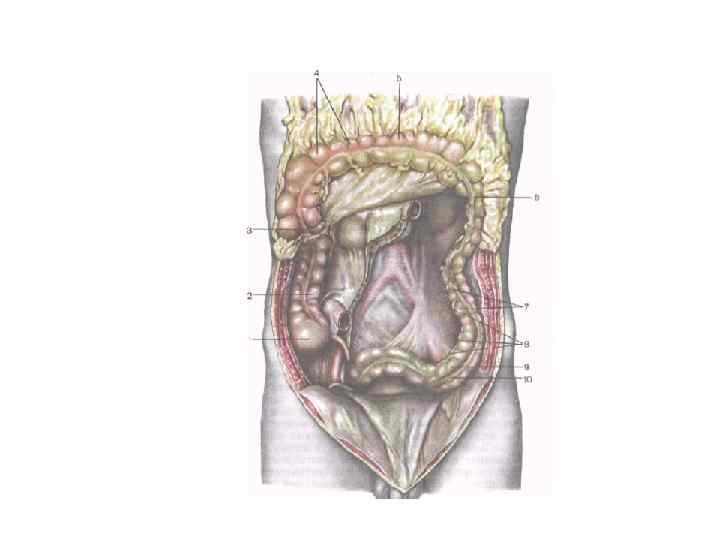

Заблуждения и факты о внутрибрюшной беременности